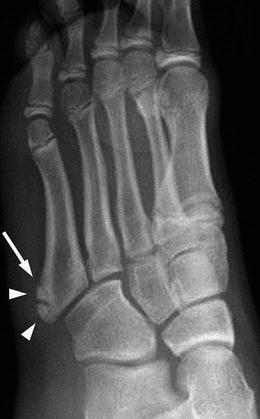

How could you tell the difference between a 5th MT base fracture in an adolescent and the normal anatomical accessory ossification centre?

Ossification centre is longitudinal, 5th MT base fractures are transverse

Arrow = normal apophysis, arrowheads are other ossification centres